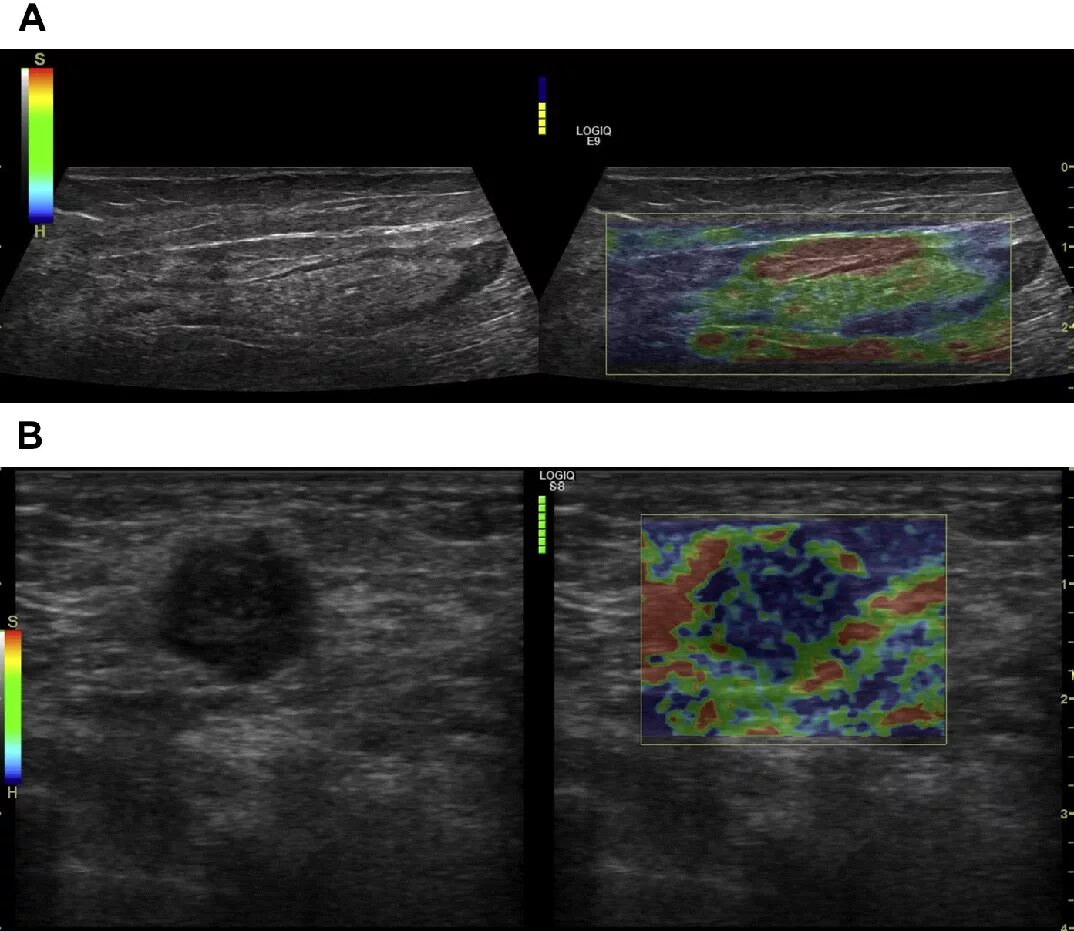

Метастазы в лимфоузлах молочной железы